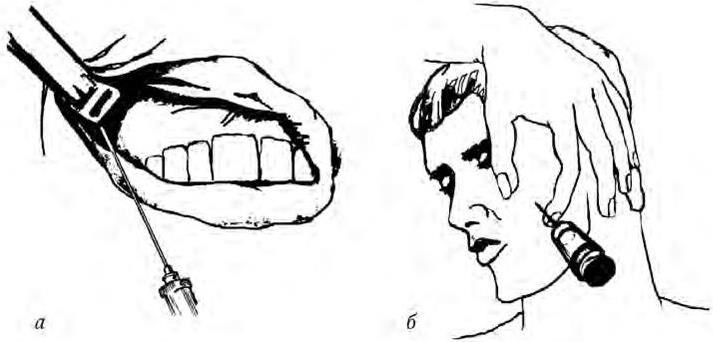

Проведенные компьютерно-томографические исследования путей распространения инъецируемого анестетика при проведении «туберальной» анестезии подтвердили высокую вероятность такого осложнения.

Рис. 1.2. Компьютерная томограмма. Спустя 5 дней после анестезии на бугре верхней челюсти четко контурируется гематома в крылонёбной ямке (указанострелкой)

На представленной компьютерной томограмме (рис. 1.2), произведенной спустя 5 дней после внутриротовой анестезии на бугре верхней челюсти, четко контурируется образовавшаяся гематома в крылонёбной ямке. Вероятность ее нагнаивания и, следовательно, развития флегмоны этого клетчатного образования велика и достигает по данным различных авторов и нашим наблюдениям 40 – 60 % (Алехова Т. М., 1989; Бажанов Н. Н. [и др.], 1998; и др.). Учитывая практическую неизбежность ранения вен крылонёбного сплетения при проведении «туберальной» анестезии и высокую вероятность развития тяжелых осложнений, особенно при использовании внутриротового способа, угрожающих здоровью и даже жизни пациента (см. главу «Воспалительные заболевания тканей челюстно-лицевой области»), применение этого вида анестезии должно быть максимально ограничено.